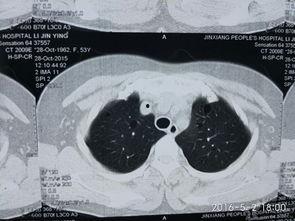

为了让你更直观地了解肺上界叩诊,我找到了一些专业的视频资料。在这些视频中,你可以看到医生们是如何操作的。他们手持木槌,在患者的胸部轻轻敲击,然后仔细聆听声音的变化。有时候,医生还会在患者的背部进行叩诊,以便更全面地了解肺部情况。

肺上界叩诊的主要目的是检查肺部是否有异常,如肺炎、肺结核等。